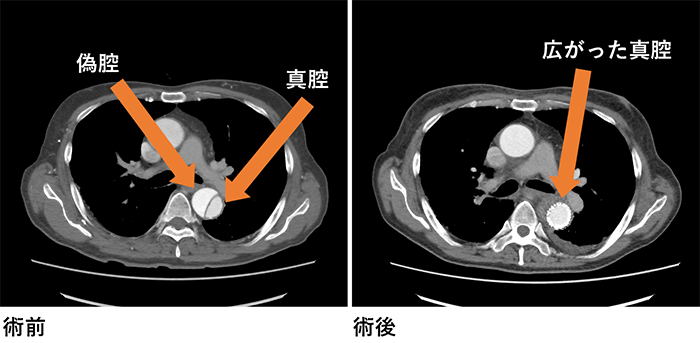

また、緊急の症例は常時24時間体制で受け入れております。特に当院は急性大動脈解離などの大動脈の緊急症例が多く、近隣の埼玉県東部地域のみならず、埼玉県内の全域および県外からもヘリコプター搬送などを利用して緊急症例を受け入れております。緊急症例により迅速に対処するため、心臓血管外科ホットラインを新たに設置し、24時間体制で心臓血管外科診療に対する電話相談を受けつております(ホットラインは医療機関からの緊急症例の相談を対象としております)。

大動脈瘤

大動脈疾患は、特に突然死の原因として心筋梗塞の次に多い疾患とも言われており、その予防と、救急対応が地域にとって重要な問題です。埼玉県東部地域における緊急手術対応可能な医療機関として、一人でも多くの人命を救助できるように、緊急手術にも積極的に対応しております。近隣の地域のみならず、緊急症例においては埼玉県全域および近隣の都道府県からのご依頼にも対応します。

胸部大動脈瘤や腹部大動脈瘤に対する治療としては、人工血管と置換する手術が基本的な根治的治療ですが、形態的な適応と年齢や手術侵襲による影響を考慮して、ステントグラフト挿入術も行っております。 他の心臓血管疾患と同様に大動脈疾患も早期発見と予防が重要です。特に大動脈疾患は、リスクファクターをお持ちの方や、ご家族に大動脈疾患を患ったことのある方には一度検査を受けることをお勧めしています。当科では、動脈硬化の評価とともに、大動脈瘤のスクリーニング検査や、動脈硬化の判定なども外来で行っております。スクリーニング検査は主にCTの大動脈の評価を行っております。